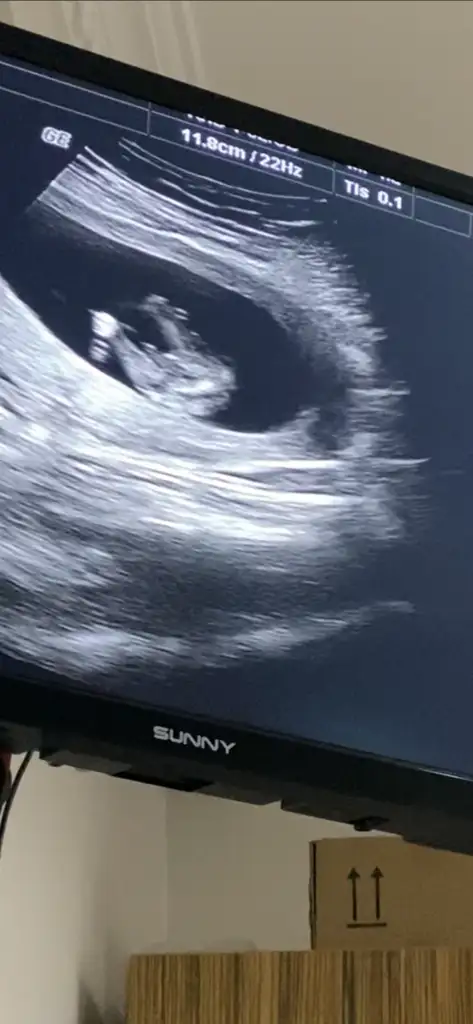

Doktorumuzda çıkıntıya göre erkek gibi ama kordonda olabilir demişti netleşince yazarımErkek sanki

Merhaba, bebeğin cinsiyeti için erkek olabilir demiştiniz ve doğru tahmin etmişsiniz. Tahmininiz için teşekkür ediyorum :)En iyi 11 12 13 haftalar olmalı